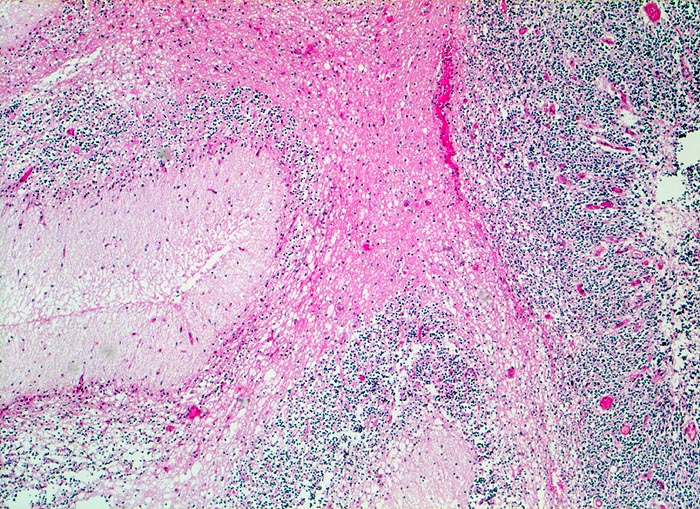

PathoPic – image database / PathoPic ID 5239 - Kleinhirn

Schlecht erhaltenes Kleinhirn angrenzend an das Medulloblastom (in diesem Bild nicht sichtbar). Kleinhirnmark, Stratum moleculare und Körnerschicht der Kleinhirnrinde.

Medulloblastom angrenzend an das Kleinhirn und die Medulla oblongata

Knabe mit Kopfschmerzen und morgendlichem Erbrechen ohne Übelkeit

Histologie

50